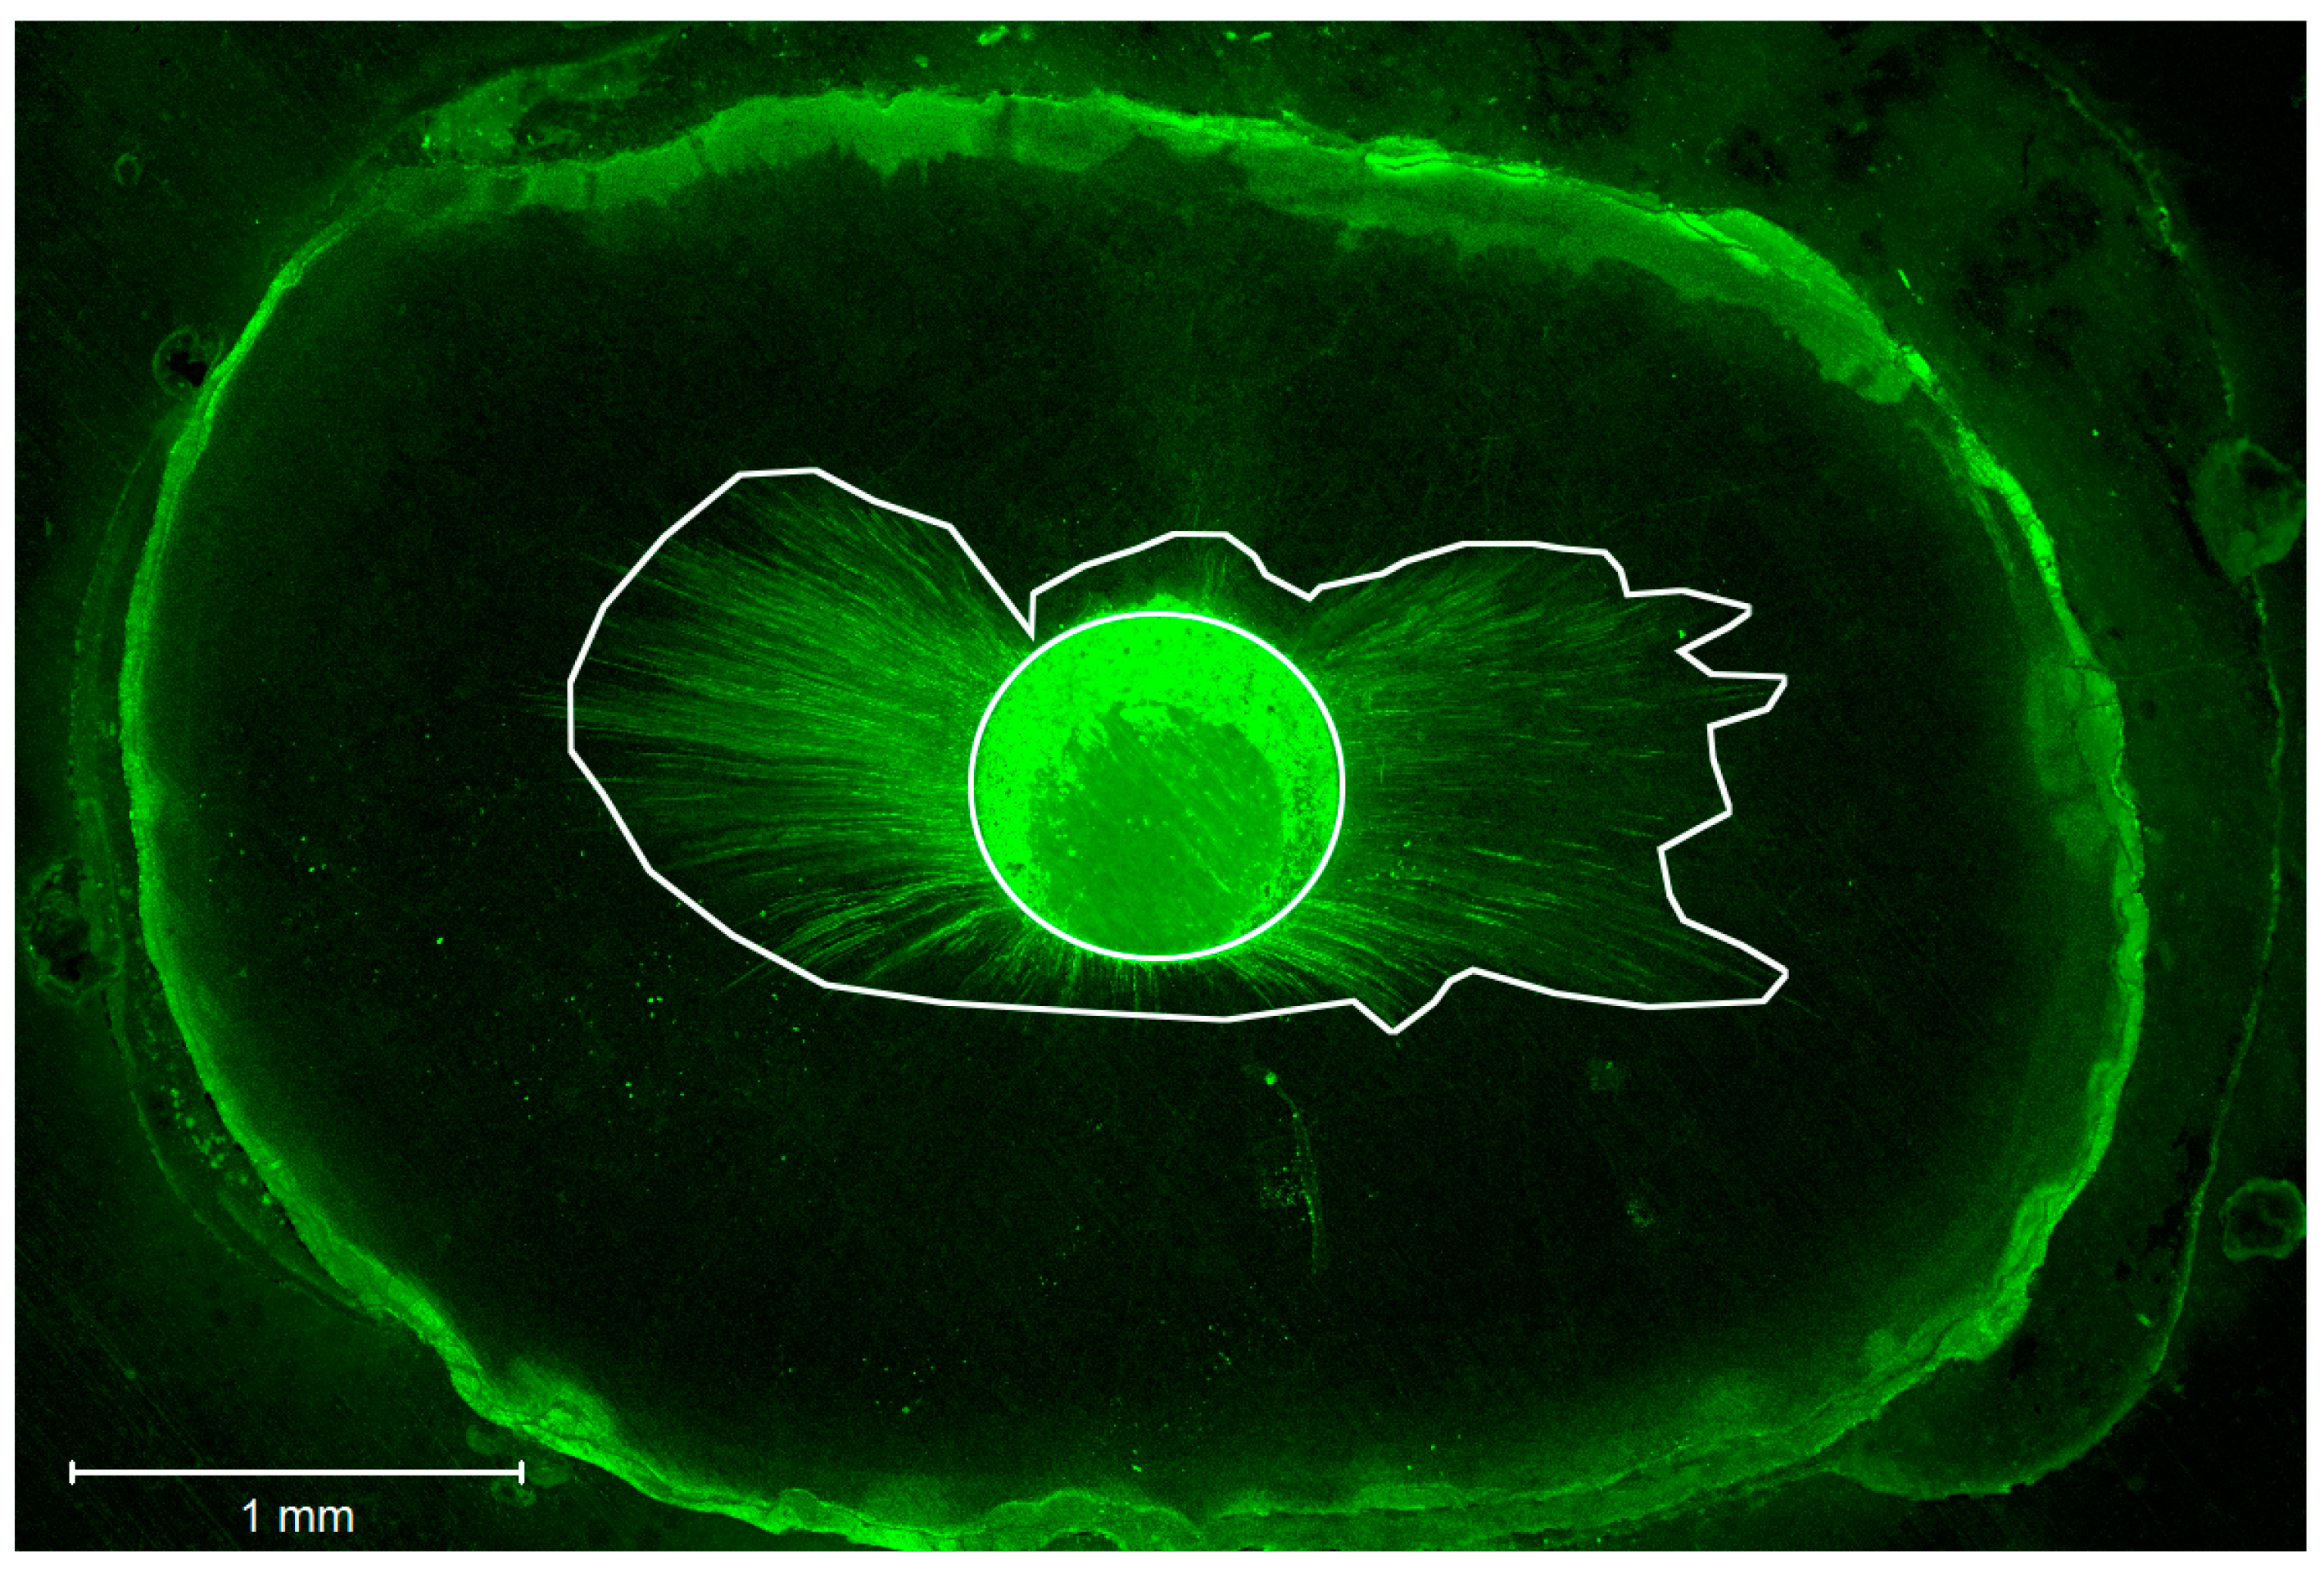

2.4. Confocal Laser Scanning Microscopic Analysis of the Roots

3.1. Sealer Penetration

3.1.1. Maximum Depth Penetration of Sealer in Dentinal Tubules

3.1.2. Mean Penetration Depth of Sealer in Dentinal Tubules

3.1.3. Circumferential Percentage of Sealer Penetration into Dentinal Tubules